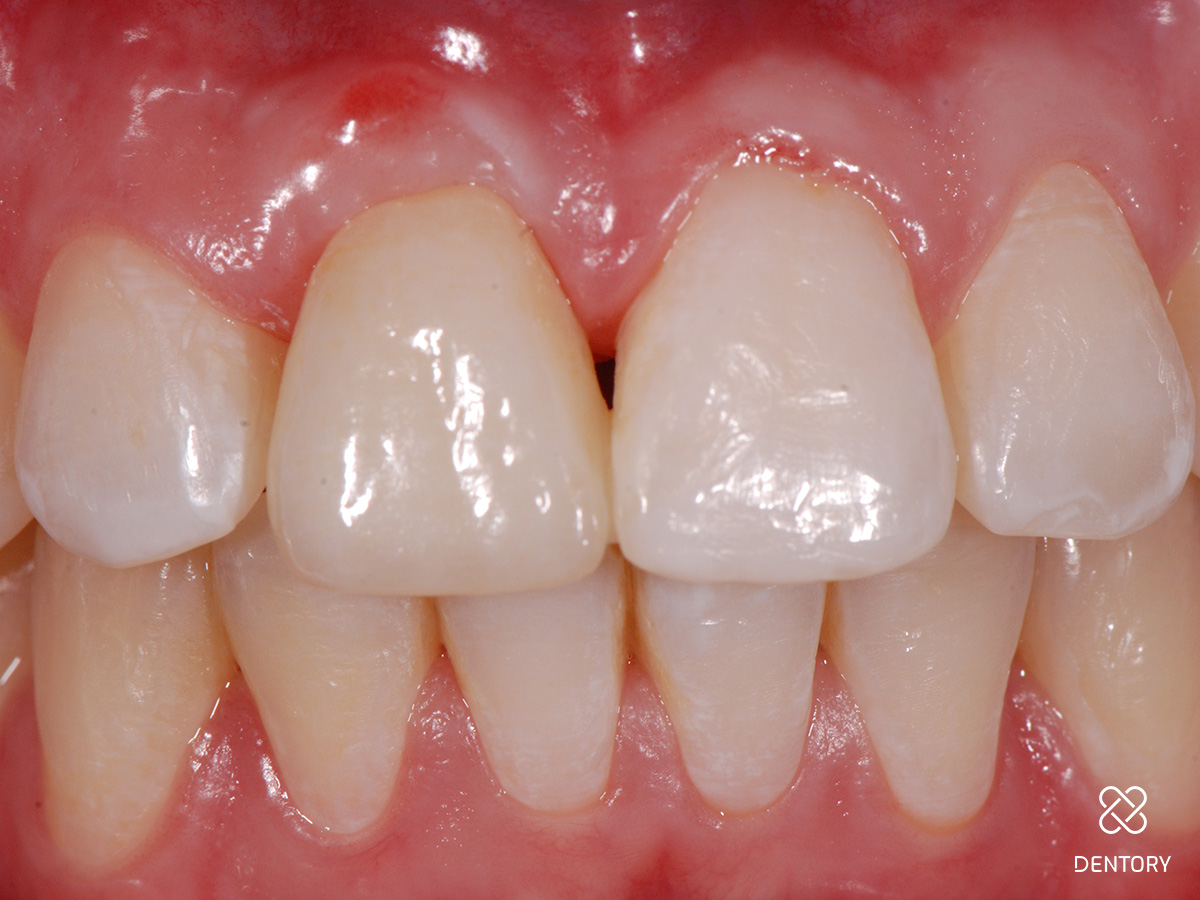

Abbildung 24

Abschlussbild.

Folgebehandlung

Bereits 2 Monate nach Zahnentfernung wurde zur mittelfristigen oder auch längerfristigen Versorgung der Lücke beim Hauszahnarzt eine vollkeramische Klebebrücke adhäsiv befestigt bis ggf. eine Implantatbehandlung gewünscht und möglich ist.

Zusammenfassung

Ein deutlicher Gewinn an Weichgewebshöhe im Vergleich zur Ausgangssituation ist sichtbar; es wurde ein symmetrischer Gingivaverlauf erzielt; die Kammbreite ist durch die Kombination aus Hart- und Weichgewebsaufbau gut erhalten geblieben.